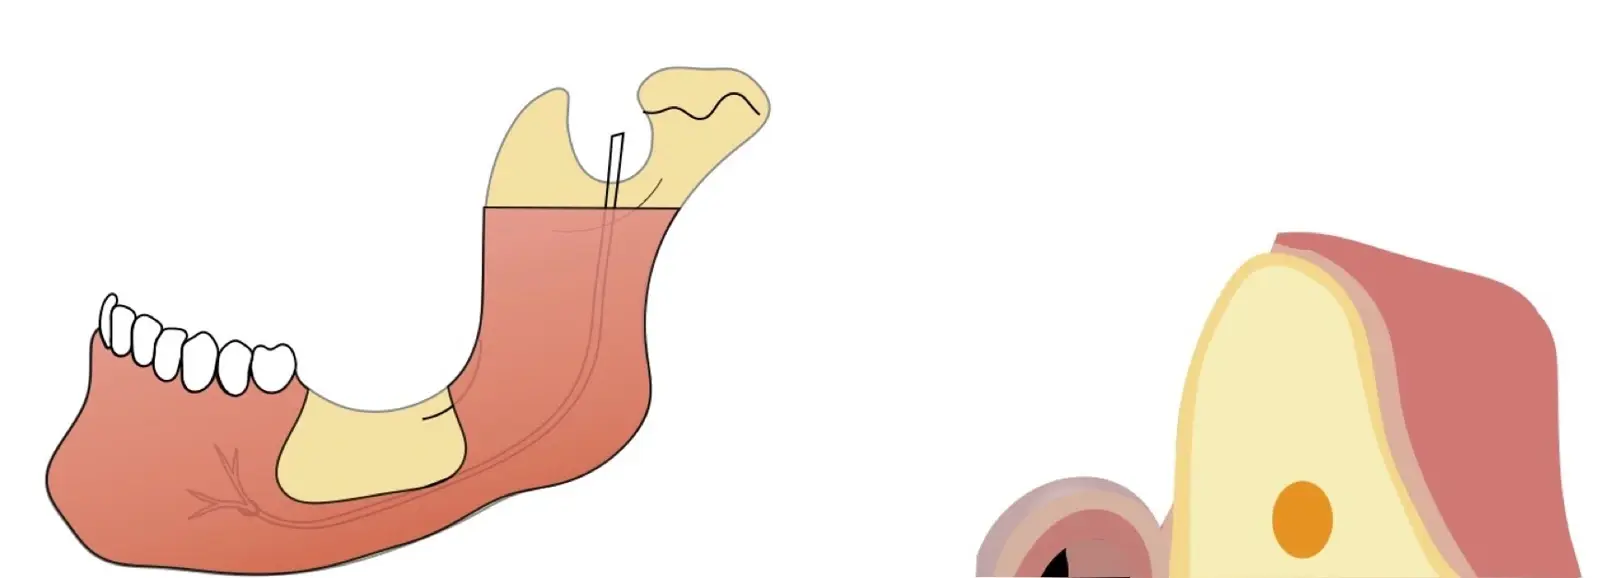

El hueso autógeno, considerado como el “gold stándard” para la regeneración ósea, no produce reacciones inmunológicas y contiene componentes osteogénicos, osteoinductores y osteoconductores.7,8 Suele obtenerse en bloques y las zonas dadoras intraorales de elección son la sínfisis mentoniana y la rama mandibular.9

La literatura menciona varias complicaciones relacionadas con la extracción de injertos óseos, la mayoría de ellas asociadas con el corte y la manipulación de zonas próximas a estructuras de riesgo; entre las más comunes, las lesiones nerviosas con consecuente adormecimiento, molestias postoperatorias (abertura bucal limitada, sangrado, hinchazón y dolor) y problemas estéticos (cambios en el contorno del área donadora o recesión de tejidos blandos).10 Aunque los injertos de rama pueden presentar menos molestias postoperatorias, tienen un acceso quirúrgico limitado debido a la apertura bucal y el peligro potencial de lesionar el paquete vásculo-nervioso cercano.11